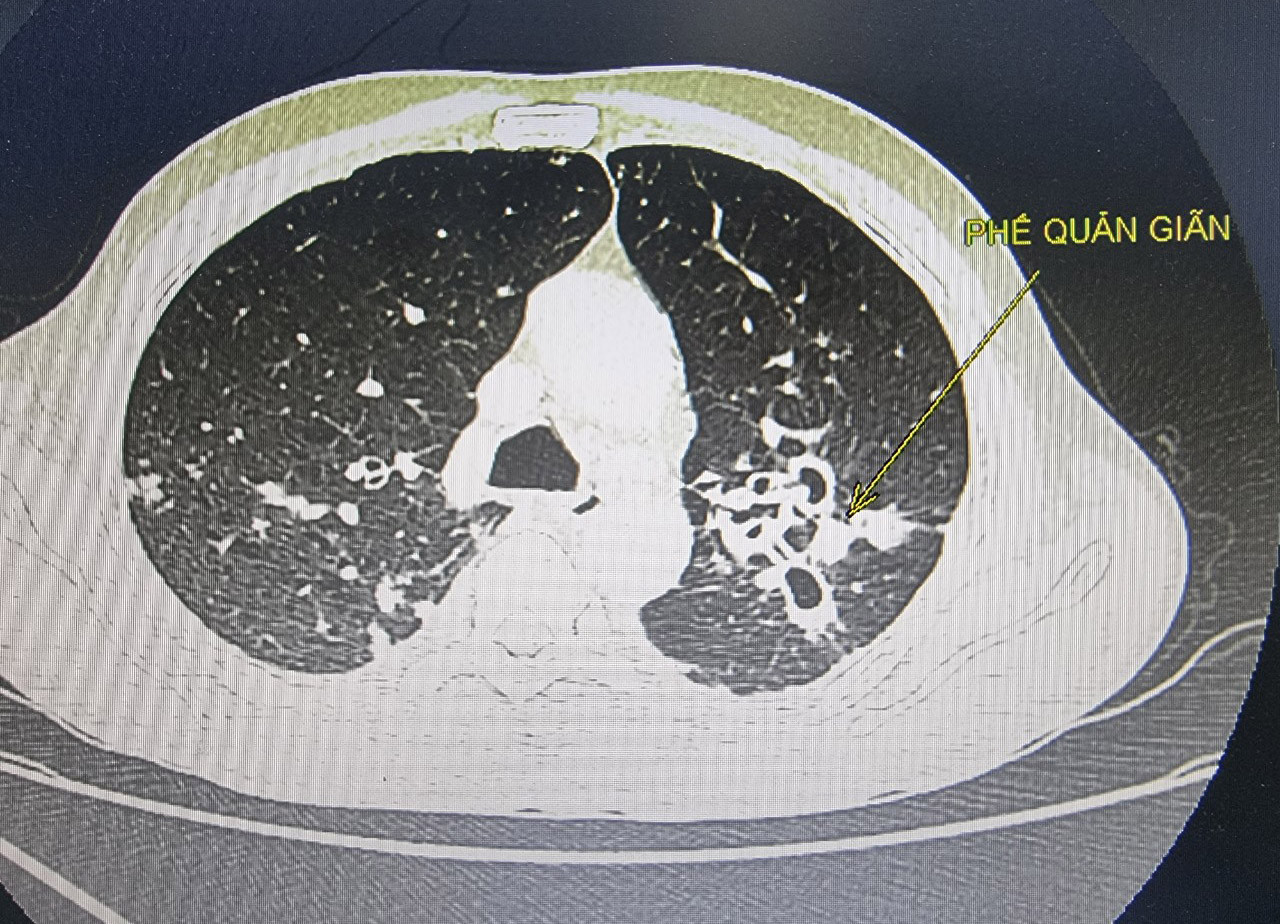

Kết quả chụp cắt lớp vi tính cho thấy bệnh nhân bị giãn phế quản hai bên phổi, động mạch phế quản hai bên giãn ngoằn ngoèo, có luồng thông với động mạch phổi. Các bác sĩ đã hội chẩn can thiệp nút động mạch phế quản cầm máu cho bệnh nhân.

Ths.BS Nguyễn Duy Thịnh thông tin thêm, giãn phế quản có nhiều nguyên nhân trong đó có liên quan tới việc hút thuốc lá kéo dài. Đối với trường hợp của bệnh nhân T. nếu không được can thiệp sớm có thể nguy hiểm tới tính mạng, do sốc mất máu hoặc có thể suy hô hấp do máu bít tắc đường thở.